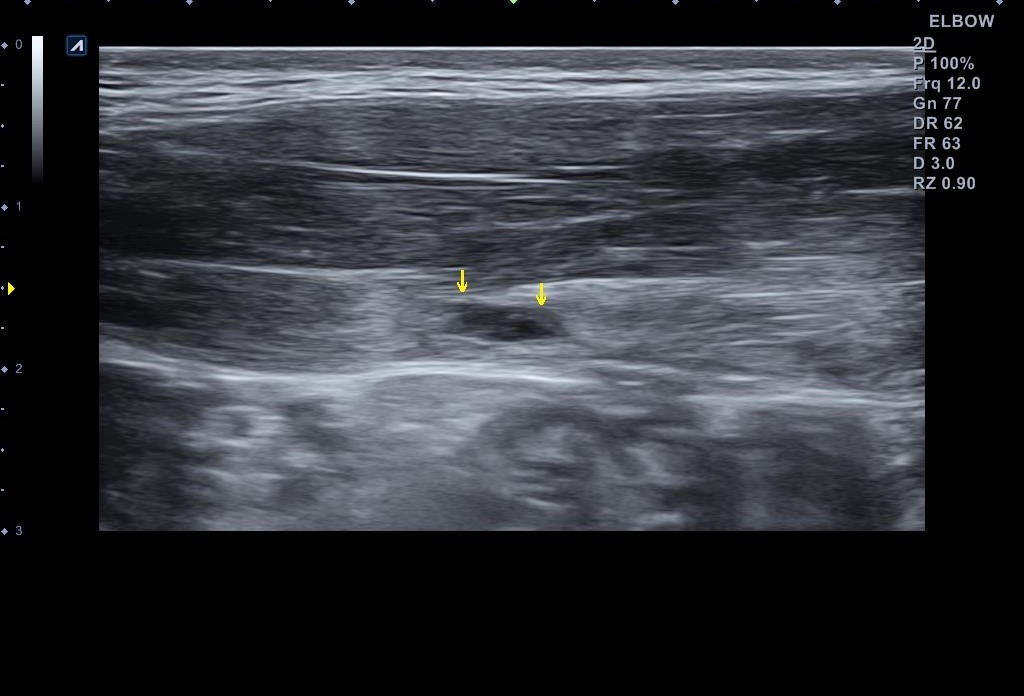

왜 슬픈 예감은 틀린적이 없을까요...일주일만에 다시 시행한 초음파 검사 상에서는... 복직근 파열이 훨씬 심해져 있었습니다.

나 : 초음파 한번 보세요.... 지난주에 비해 파열 크기가 훨씬 커졌어요... 근육에 빵꾸가 2개나 나버렸어요...

환자의 증상이 심해진만큼 복직근 파열도 훨씬 심해져 있었습니다. 보통 근육은 혈관 분포가 풍부해서 왠만큼 찢어져도 잘 붙는 조직입니다. 문제는 일상 생활에서는 근육 파열 통증이 금방 사라지기 때문에 완전히 회복하지 않은 상태에서 운동을 다시 하는 경우가 많고 그러다가 재파열이 흔하게 발생한다는 점입니다.

이런 경우에는 초음파 검사를 1~2주 간격으로 시행해서 근육 손상이 회복된것을 정확히 확인 후 운동을 복귀해야 부상의 재발을 막을 수 있습니다.